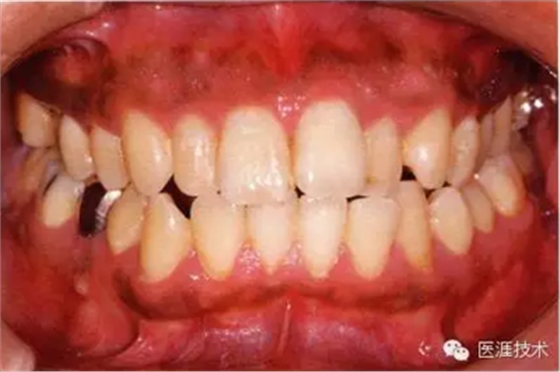

14歲男性牙齦炎的臨床圖像